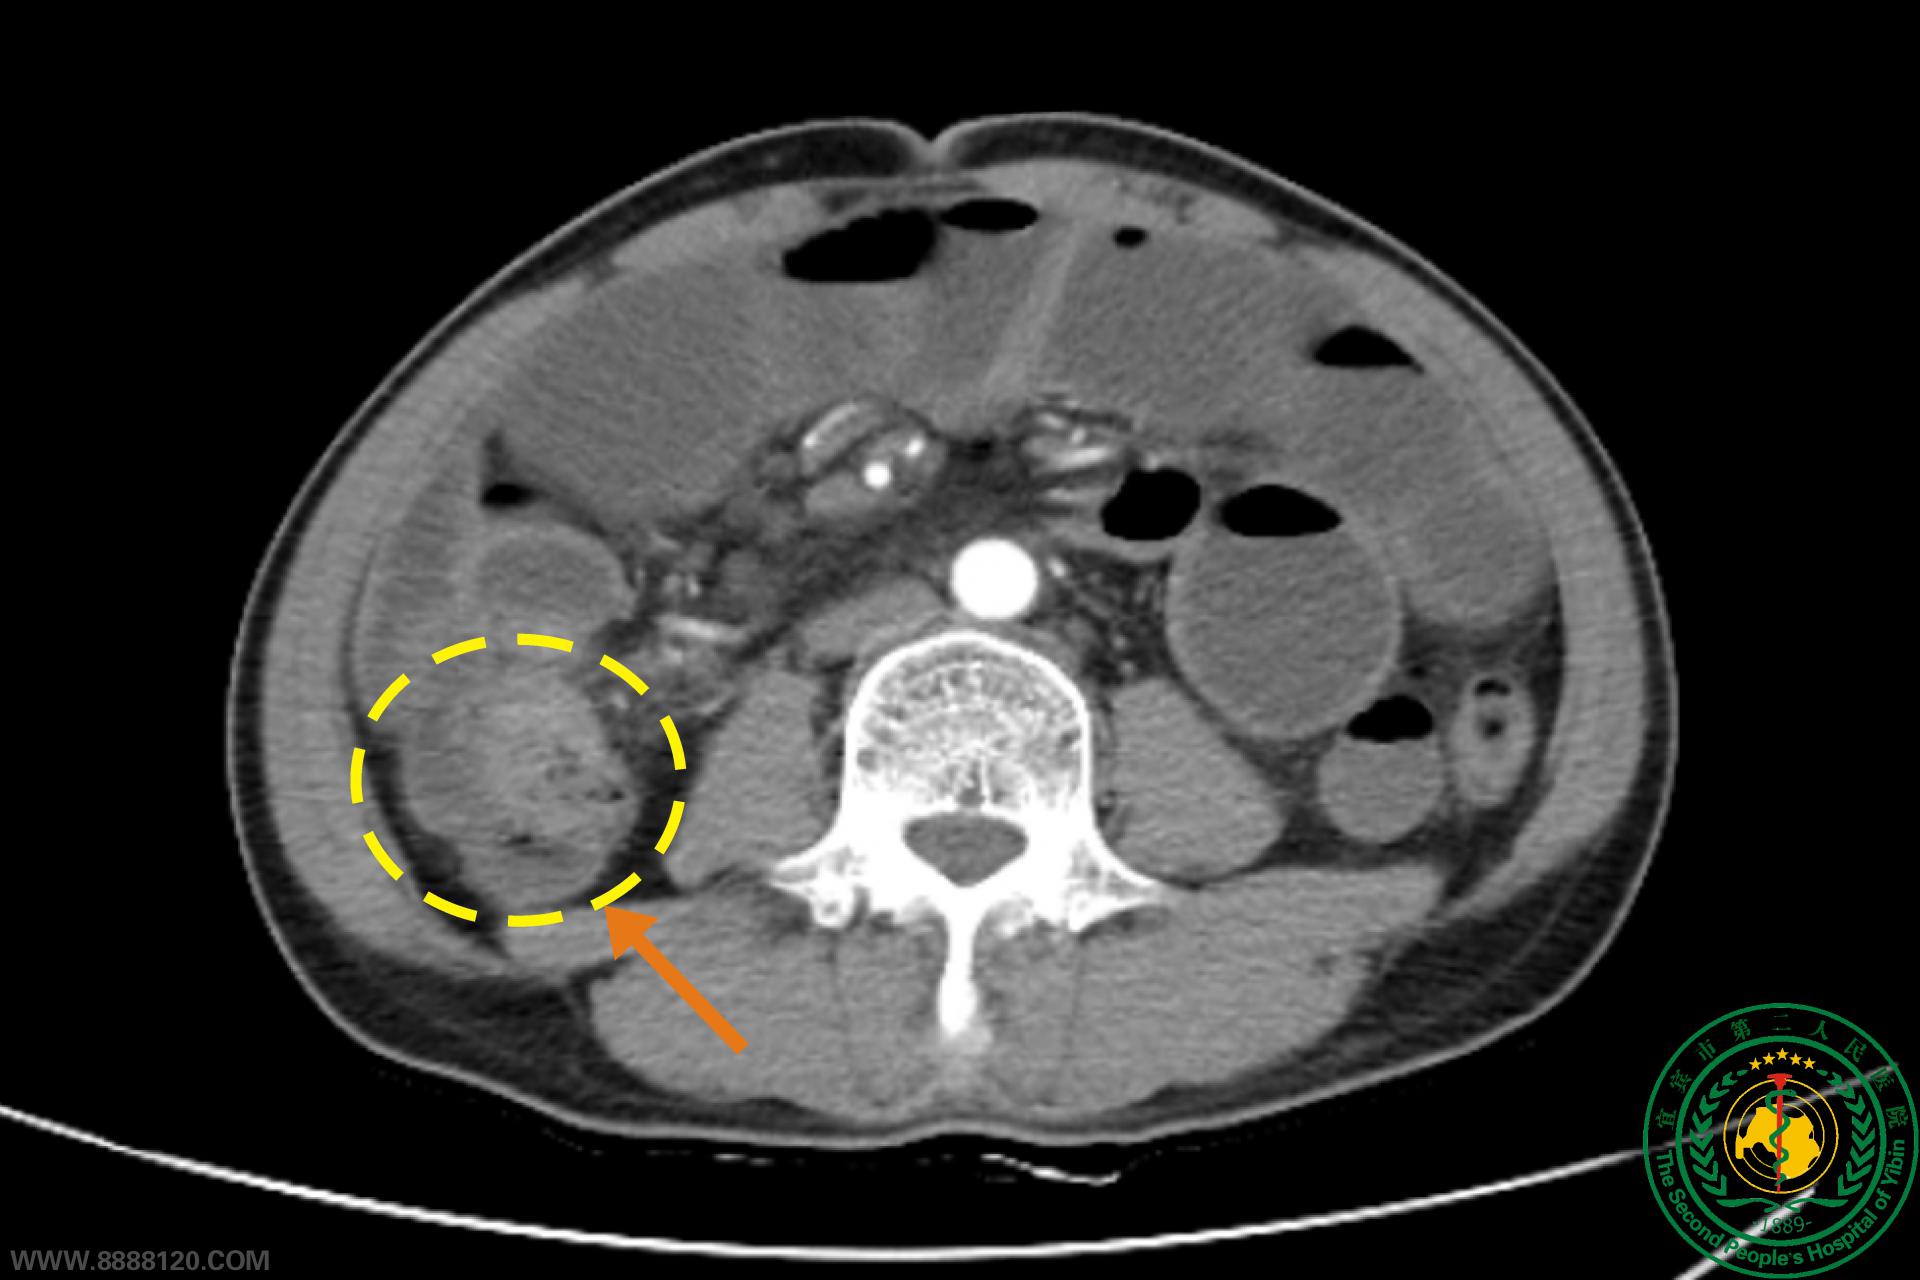

梗阻性结肠癌也可以做腹部无切口根治性手术

梗阻性结肠癌也可以做腹部无切口根治性手术54054

宜宾市第二人民医院 图文